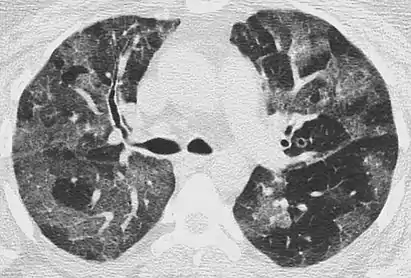

The diffuse pattern typically refers to GGOs in multiple lobes of one or both lungs. Broadly, a diffuse pattern of GGO can be caused by displacement of air with fluid, inflammatory debris, or fibrosis. Cardiogenic pulmonary edema and ARDS are common causes of a fluid-filled lung. Diffuse alveolar hemorrhage is a rarer cause of diffuse GGO seen in some types of vasculitis, autoimmune conditions, and bleeding disorders.[6]

Inflammation and fibrosis can also cause diffuse GGOs. Pneumocystis pneumonia, an infection typically seen in immunocompromised (e.g. patients with AIDS) or immunosuppressed individuals, is a classic cause of diffuse GGOs. Many viral pneumonias and idiopathic interstitial pneumonias can also lead to a diffuse GGO pattern. Radiation pneumonitis, a side effect of pulmonary radiation therapy, can lead to pulmonary fibrosis and diffuse GGOs.[6]